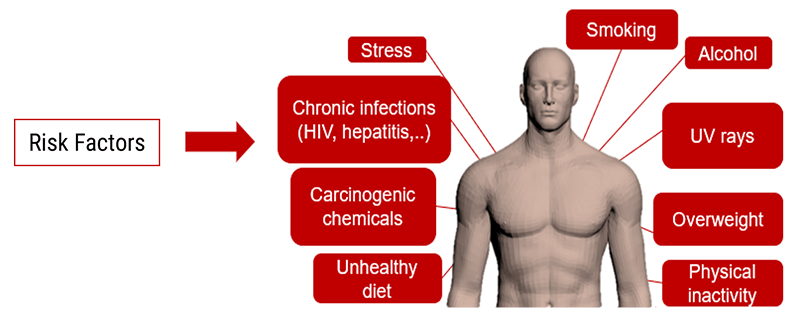

Risk Factors

Identifying patients with risk factors is very important. It is important to identify patients with risk factors in order to take appropriate measures to diminish the importance and consequences of renal failure induced by contrast injection.

For children and elderly patients, the contrast clearance is low. It is important to perform lab analysis prior to any injection of contrast media to verify that renal failure will not be an issue.

High-Risk Concerns

Certain patients are considered high risk and pose additional concerns when using contrast media.